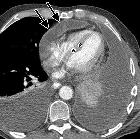

CT

CT is very sensitive in demonstrating calcification of the pericardium which is suggestive of the disease if found in the proper clinical setting. A thickened pericardium (>4 mm) on its own does not indicate constrictive pericarditis . Contrast-enhanced CT may also show signs of cardiac failure like septal flattening and retrograde flow of contrast into the dilated inferior vena cava and hepatic veins.